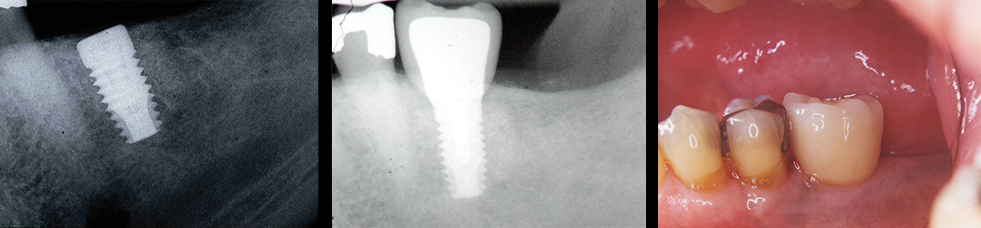

Implant Dentistry

A dental implant is a choice of treatment to replace a missing tooth or teeth. Dental implants have a remarkable success rate. There are many factors that go into the process involved in the planning and surgical placement of dental implants. Is there enough bone… is it good quality? …is it in the right place? …is it mature enough to hold

an implant?

We assess these and many more such factors before proceeding with any treatment. Dental implants are another treatment option for missing teeth you may wish to explore with Dr. Sterrett.

Bone Grafting for Implants

The amount of bone present at an implant site is a key factor in successful implant dentistry. We first assess bone volume with our in-office cone bean CT or CBCT. If the bone is not present in the desired location, then one must grow bone through a process known as “guided bone regeneration” or “GBR. There are 3 main procedures we use to induce the body to fill in areas found to be deficient in bone i.e. 1) socket grafting, 2) ridge grafting, and 3) sinus grafting.